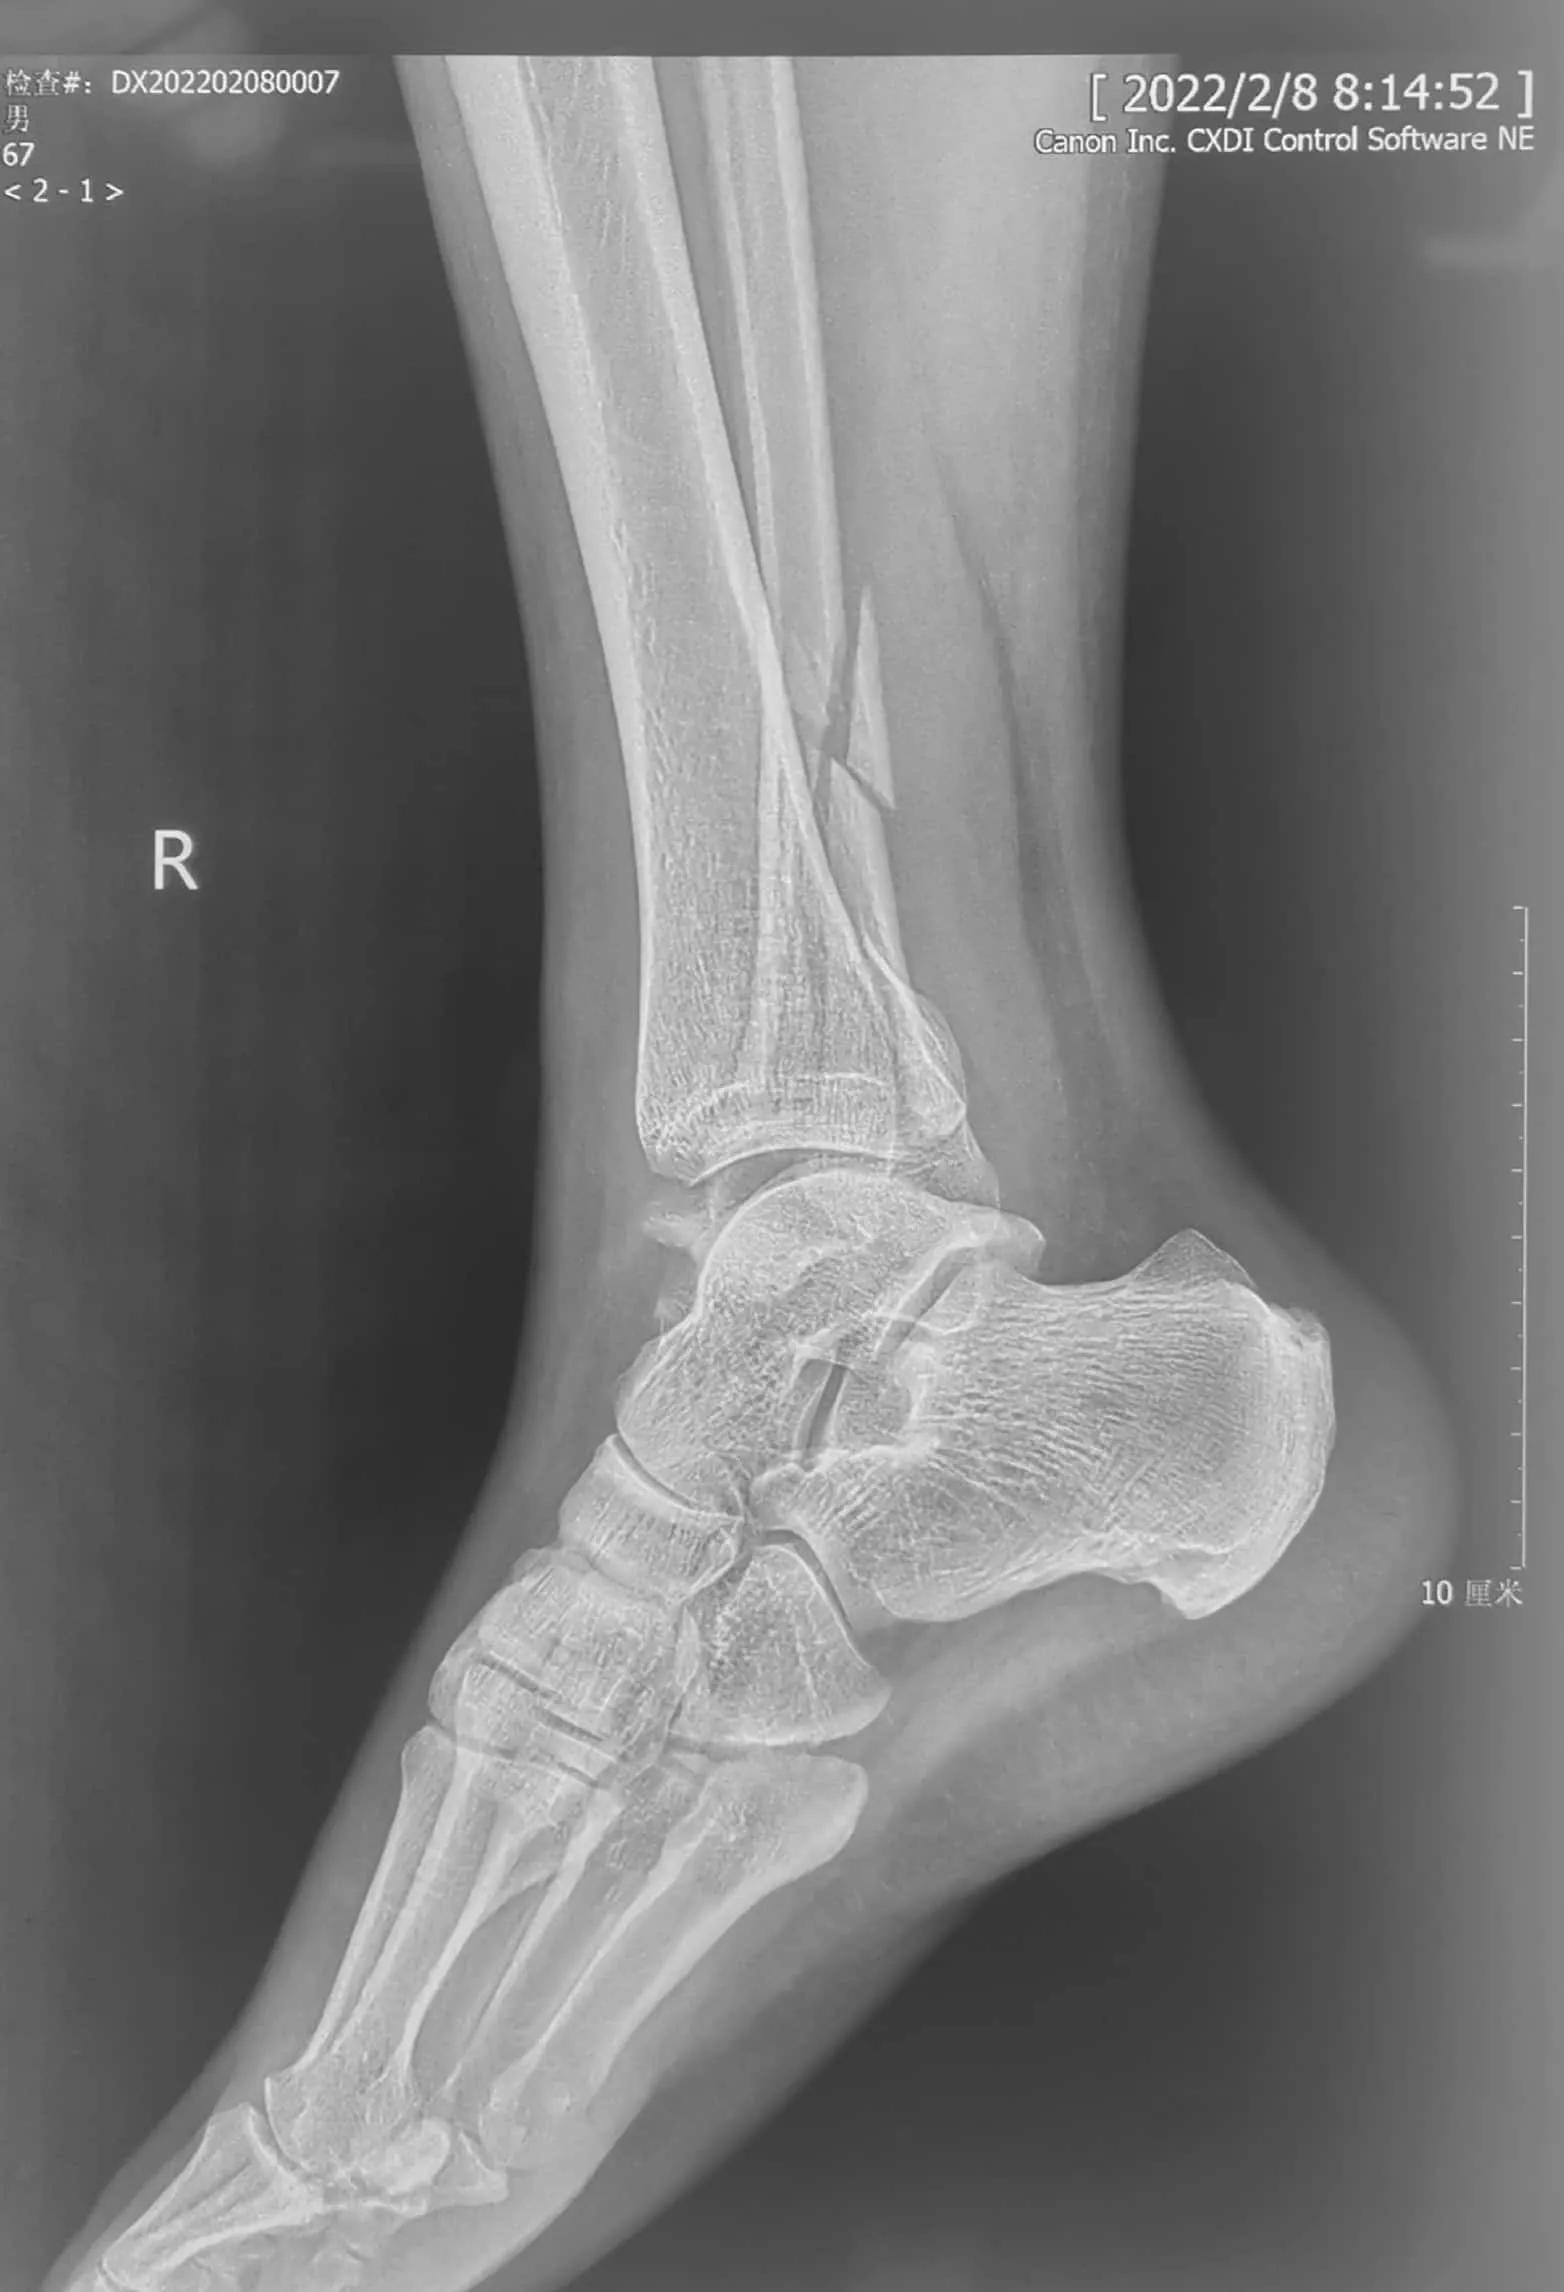

45岁,男性,2022年1月20日,也就是春节前10天不慎扭伤踝关节,过了两天到医院检查,诊断踝关节骨折。就近住院了,据说因为受伤太肿胀了,又临近春节,竟然让患者出院回家休养。17天了,患者仍疼痛难忍,踝关节肿胀。昨天来到我们医院,又拍了一次片子,竟然还和第一次检查时的片子一样,踝关节骨折脱位,内踝交锁!

这个踝关节骨折够严重的吧!